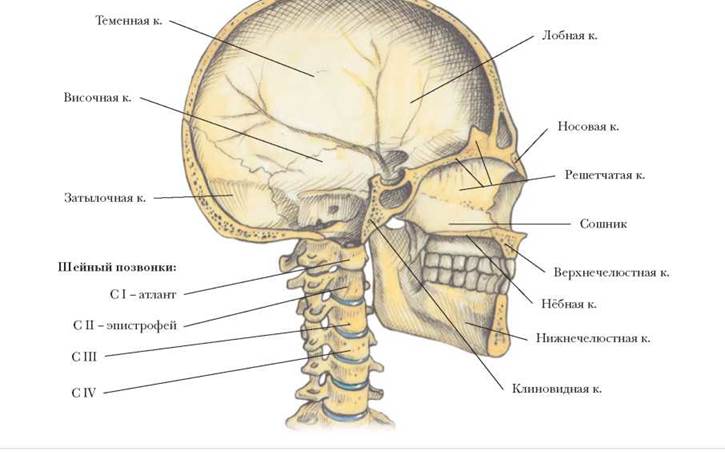

Анатомические детали: Фотографии топографии черепа с нижнего вида

Раздел: Альбом идей